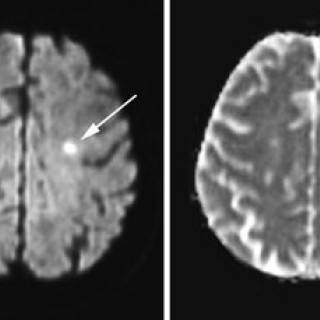

Tema: Hjerneslag